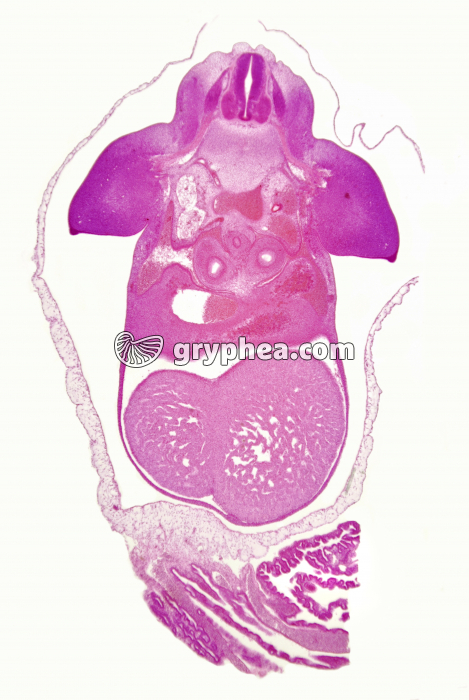

Embryon de Porc de 10mm CT x4

Embryon de Porc de 10mm CT x4 - gryphea.org